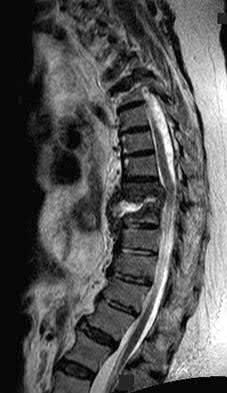

Figures 9a through 9c are the MRI scans of a 65-year-old woman on dialysis who has thoracic back pain, malaise, and an elevated erythrocyte sedimentation rate (ESR). The clinical history and imaging findings are most consistent with

Corrent answer: 3

The sagittal MRI scans are pathognomonic for diskitis and osteomyelitis with fluid signal and destructive changes in the disk on T2 (Figure 9a), low signal with blurring of the disk margins on T1 (Figure 9b), and on the T1 gadolinium image (Figure 9c) vertebral body enhancement on either side of the affected disk with dark signals within the disk corresponding to the bright fluid signal from the T2 image. Metastatic carcinoma tends to affect the vertebral body with relative disk sparing, and lymphoma can affect the vertebral body but often has soft tissue extending within the spinal canal. Osteoporotic fractures are contained with the vertebral body. Renal osteodystrophy can result in a diskitis picture with disk destruction but one would not expect an elevated ESR or malaise, and this is much rarer than diskitis in dialysis patients.